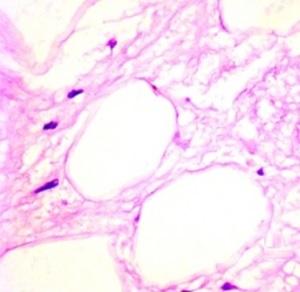

Les mammifères, dont les humains, ont 2 types de tissus adipeux, blanc et brun. Le tissu adipeux blanc (White adipose tissue- WAT), a une faible capacité à brûler l’énergie et est donc associé à un gain de poids et à l’obésité, ainsi qu’à d’autres troubles métaboliques, dont l’hypercholestérolémie, l’hypertension artérielle (HTA) et la résistance à l’insuline (pré-diabète). Combiné à l’excès de poids, cette graisse blanche abdominale est précurseur de syndrome métabolique, un syndrome lié au risque de maladie cardiaque et de diabète.

En revanche, le tissu adipeux brun (Brown adipose tissue- BAT), brûle de l’énergie à un rythme beaucoup plus rapide, dans un processus appelé thermogenèse. En raison de cette consommation accélérée d’énergie, BAT est un terrain de plus en plus privilégié de recherche de nouveaux traitements contre l’obésité. En particulier, l’objectif de pouvoir transformer « WAT » en « BAT » est l’objectif de nombreuses recherches.

En induisant ainsi la graisse blanche à la thermogenèse, le composé GC-1 apporte aux cellules graisseuses la capacité d’éliminer les calories en excès, en les convertissant à la chaleur au lieu de les stocker sous forme de masse adipeuse.